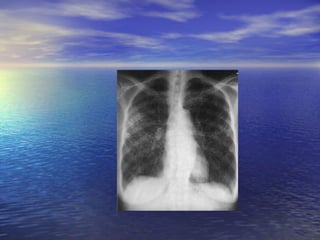

Cavitary pulmonary tuberculosis

Reinfetion(chronic) pulmonary Endogenous/exogenous differs from initial form: apex of the lung, cavitation, little or no hilar glandular enlargement fever, malaise, anorexia, weight loss, anemia, cough, chest pain Hemoptysis does not occur as commonly in children as in adults.

Reinfetion(chronic) pulmonary Endogenous/exogenousdiffers from initial form: apex of the lung, cavitation, little or no hilar glandular enlargement fever, malaise, anorexia, weight loss, anemia, cough, chest pain Hemoptysis does not occur as commonly in children as in adults.